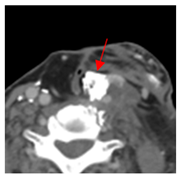

| 1 | 75–100 | 860 | ![]() Axial post-contrast fat-suppressed T1-weighted MRI shows a solidly enhancing left retroarticular tumor. | ![]() Axial CT image obtained 1 day after injection shows the NBTXR3 nanoparticles (arrows) in the tumor with leakage into the surrounding soft tissues. |